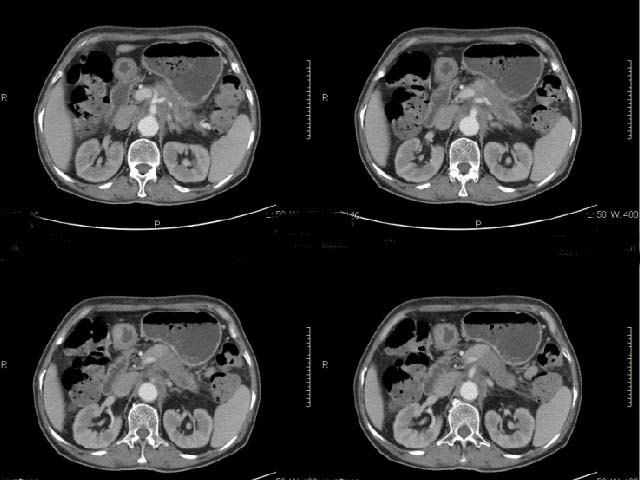

女,69岁,浑身乏力,腹泻半年余,无腹疼,排泄物中含有脂肪球,抗炎治疗一周仍不缓解,来我院检查发现明显低钾血症,给予补钾(氯化钾)一周后,血钾恢复正常,经化验检查,尿钾持续明显高于正常,临床考虑患者不仅消化道失钾,还伴有泌尿系统失钾,故进行ct增强检查看肾上腺是否有病变。ct表现为胰腺肥大,而且体尾部强化较弱,明显呈稍低密度,胰尾见有更低密度,而且胰腺与周围组织的脂肪间隙不清,大血管周围似乎有包绕现象,患者是否有过胰腺炎病史,家属说不清楚;而双侧肾上腺大小形态,本人认为未见异常,本人倾向于考虑:慢性胰腺炎伴假性囊肿,不排除胰腺占位可能;但是不知怎么解释持续尿钾现象。请大家发表高见!

动脉期